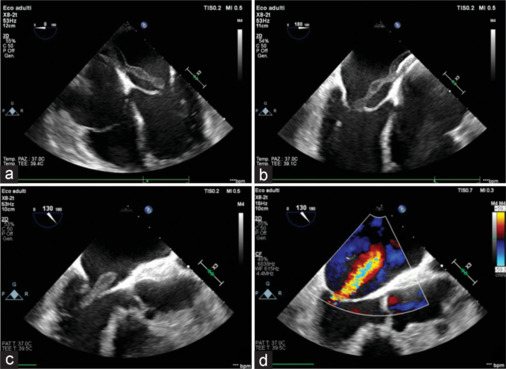

Patent foramen ovale (PFO) is a congenital cardiac defect present in approximately 30% of the general population. While often asymptomatic, it is associated with cryptogenic stroke and paradoxical embolism. Percutaneous closure using atrial septal defect occluder is an effective preventive strategy, but these devices carry a risk of rare complications, including infective endocarditis. Device-associated infective endocarditis is often linked to transient bacteremia following invasive procedures, highlighting the importance of antibiotic prophylaxis. However, the clinical presentation can be variable, requiring a high index of suspicion and advanced imaging for the diagnosis. We describe the case of a 55-year-old woman with hypertension, obesity, and a history of PFO closure with an Amplatzer occluder, who developed infective endocarditis weeks after a dental procedure. She presented with fever, vomiting, and confusion, initially misdiagnosed with encephalitis. Transesophageal echocardiography revealed large filamentous vegetation on the Amplatzer occluder, causing functional mitral regurgitation. Blood cultures identified Staphylococcus aureus and Streptococcus pneumoniae, confirming a mixed bacterial infection. The patient underwent surgical removal of the infected device and mitral valve repair. Postoperatively, she improved significantly and was discharged with a complete course of antibiotics. This case underscores the need for vigilance in patients with intracardiac devices, particularly following bacteremia-inducing procedures. Early diagnosis using echocardiography and prompt surgical intervention are essential to managing device-related infective endocarditis. While antibiotic prophylaxis may reduce the risk of bacteremia-related infections, the lack of high-quality evidence necessitates further research to guide preventive strategies. Multidisciplinary care and strict adherence to diagnostic and therapeutic protocols remain pivotal to improving patient outcomes.